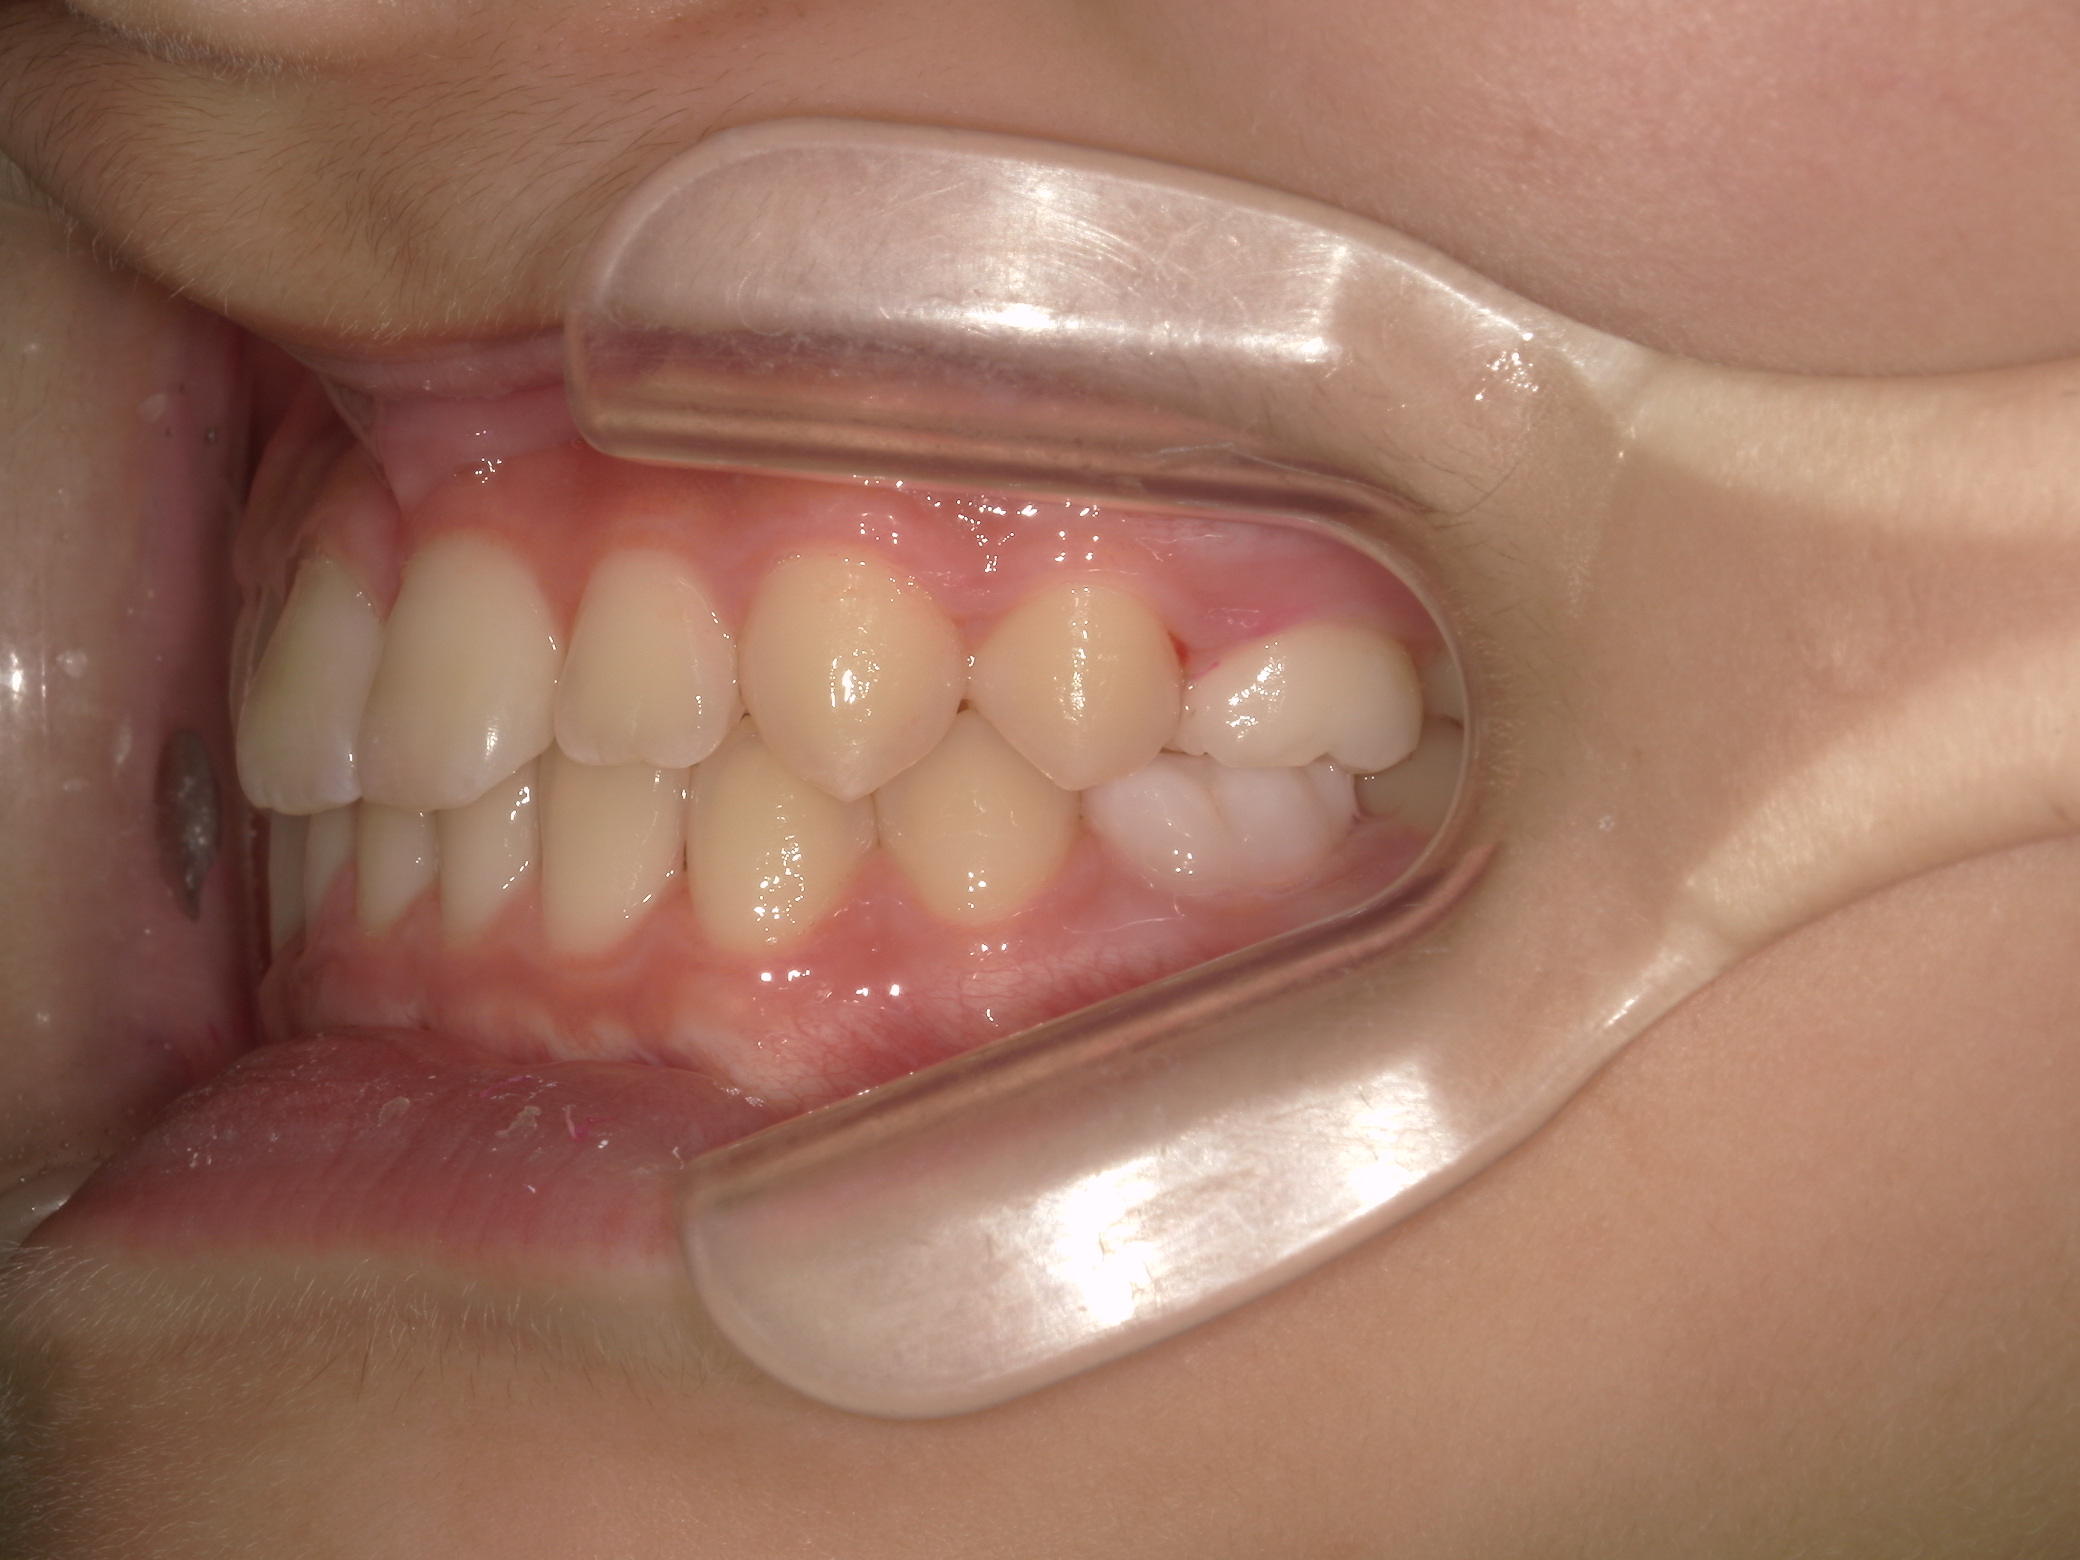

【小学生】マイオブレース矯正 反対咬合を改善

小学生で開始

マイオブレース

受け口

非抜歯

1期治療のみで改善

Before

After

治療期間

1.6年

治療開始

8歳

種類

マイオブレース矯正

使用装置

機能矯正装置

コメント

治療にしっかり取り組んでくれたのでスムーズに治りました。

治療後3年経過した今でも 装置もいれずに 後戻りもしていません。